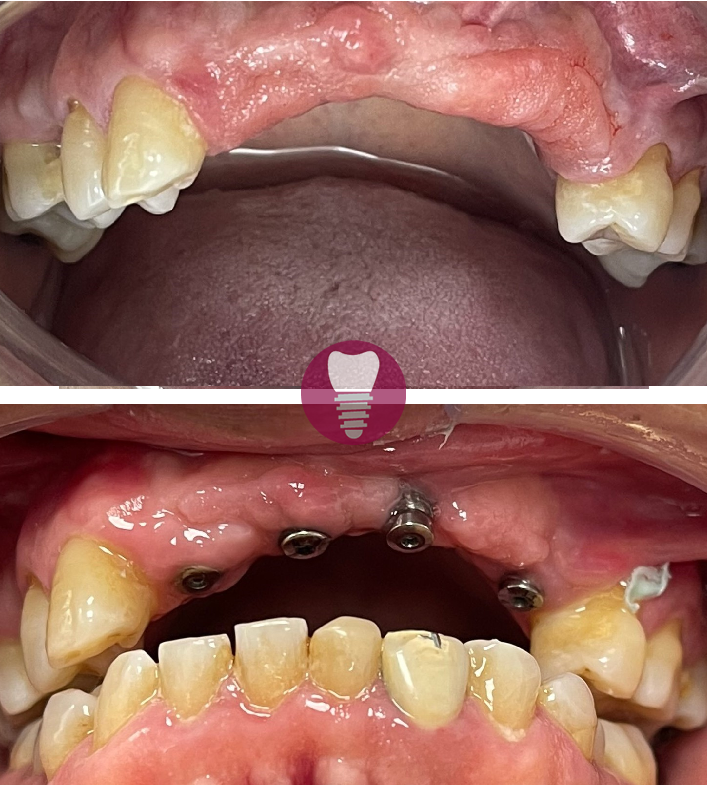

Este caso clínico muestra un tratamiento de restauración completa de la dentadura superior. Este tipo de intervención es ideal para pacientes que presentan una pérdida significativa de piezas dentales en la arcada superior o que tienen dientes gravemente dañados debido a caries avanzadas, desgaste, o problemas periodontales.

En este tratamiento, se emplea una prótesis sobre barra en implantes, proporcionando una solución estable y estética que permite recuperar la funcionalidad y la apariencia de la sonrisa. Este enfoque no solo mejora la capacidad de masticación del paciente, sino que también refuerza la estructura facial y restaura la confianza en su aspecto.

Gracias a la planificación digital y los materiales de alta calidad utilizados, el resultado es duradero y natural.